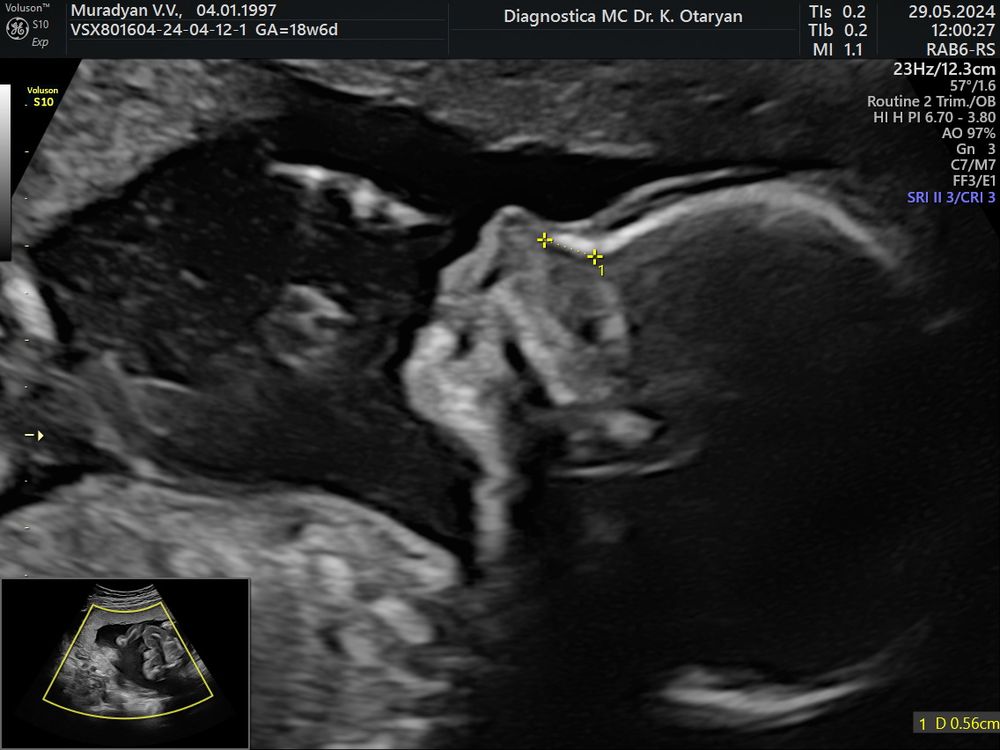

2-ой скрининг , 18 недель 6 дней. 29.05 💖

Малыш развивается хорошо, опережает срок на 4 дня, по размерам ставят 19 недель 4 дня.

ПДР ставят , как и на первом скрининге , раньше, чем по месячным, на 20.10

плацента так и не поднялась пока, 2,2 см от внутреннего зева ( да еще и обвился пуповиной, но врач сказала на этом сроке ничего страшного.

Вес у человека 298 грамм уже 🥹, во всю двигается, шевеления чувствую по вечерам в основном и пару раз днём, на узи носик по-моему мой💖 врач сказала все отлично, здоровенький, малыш дал рассмотреть себя со всех сторон)